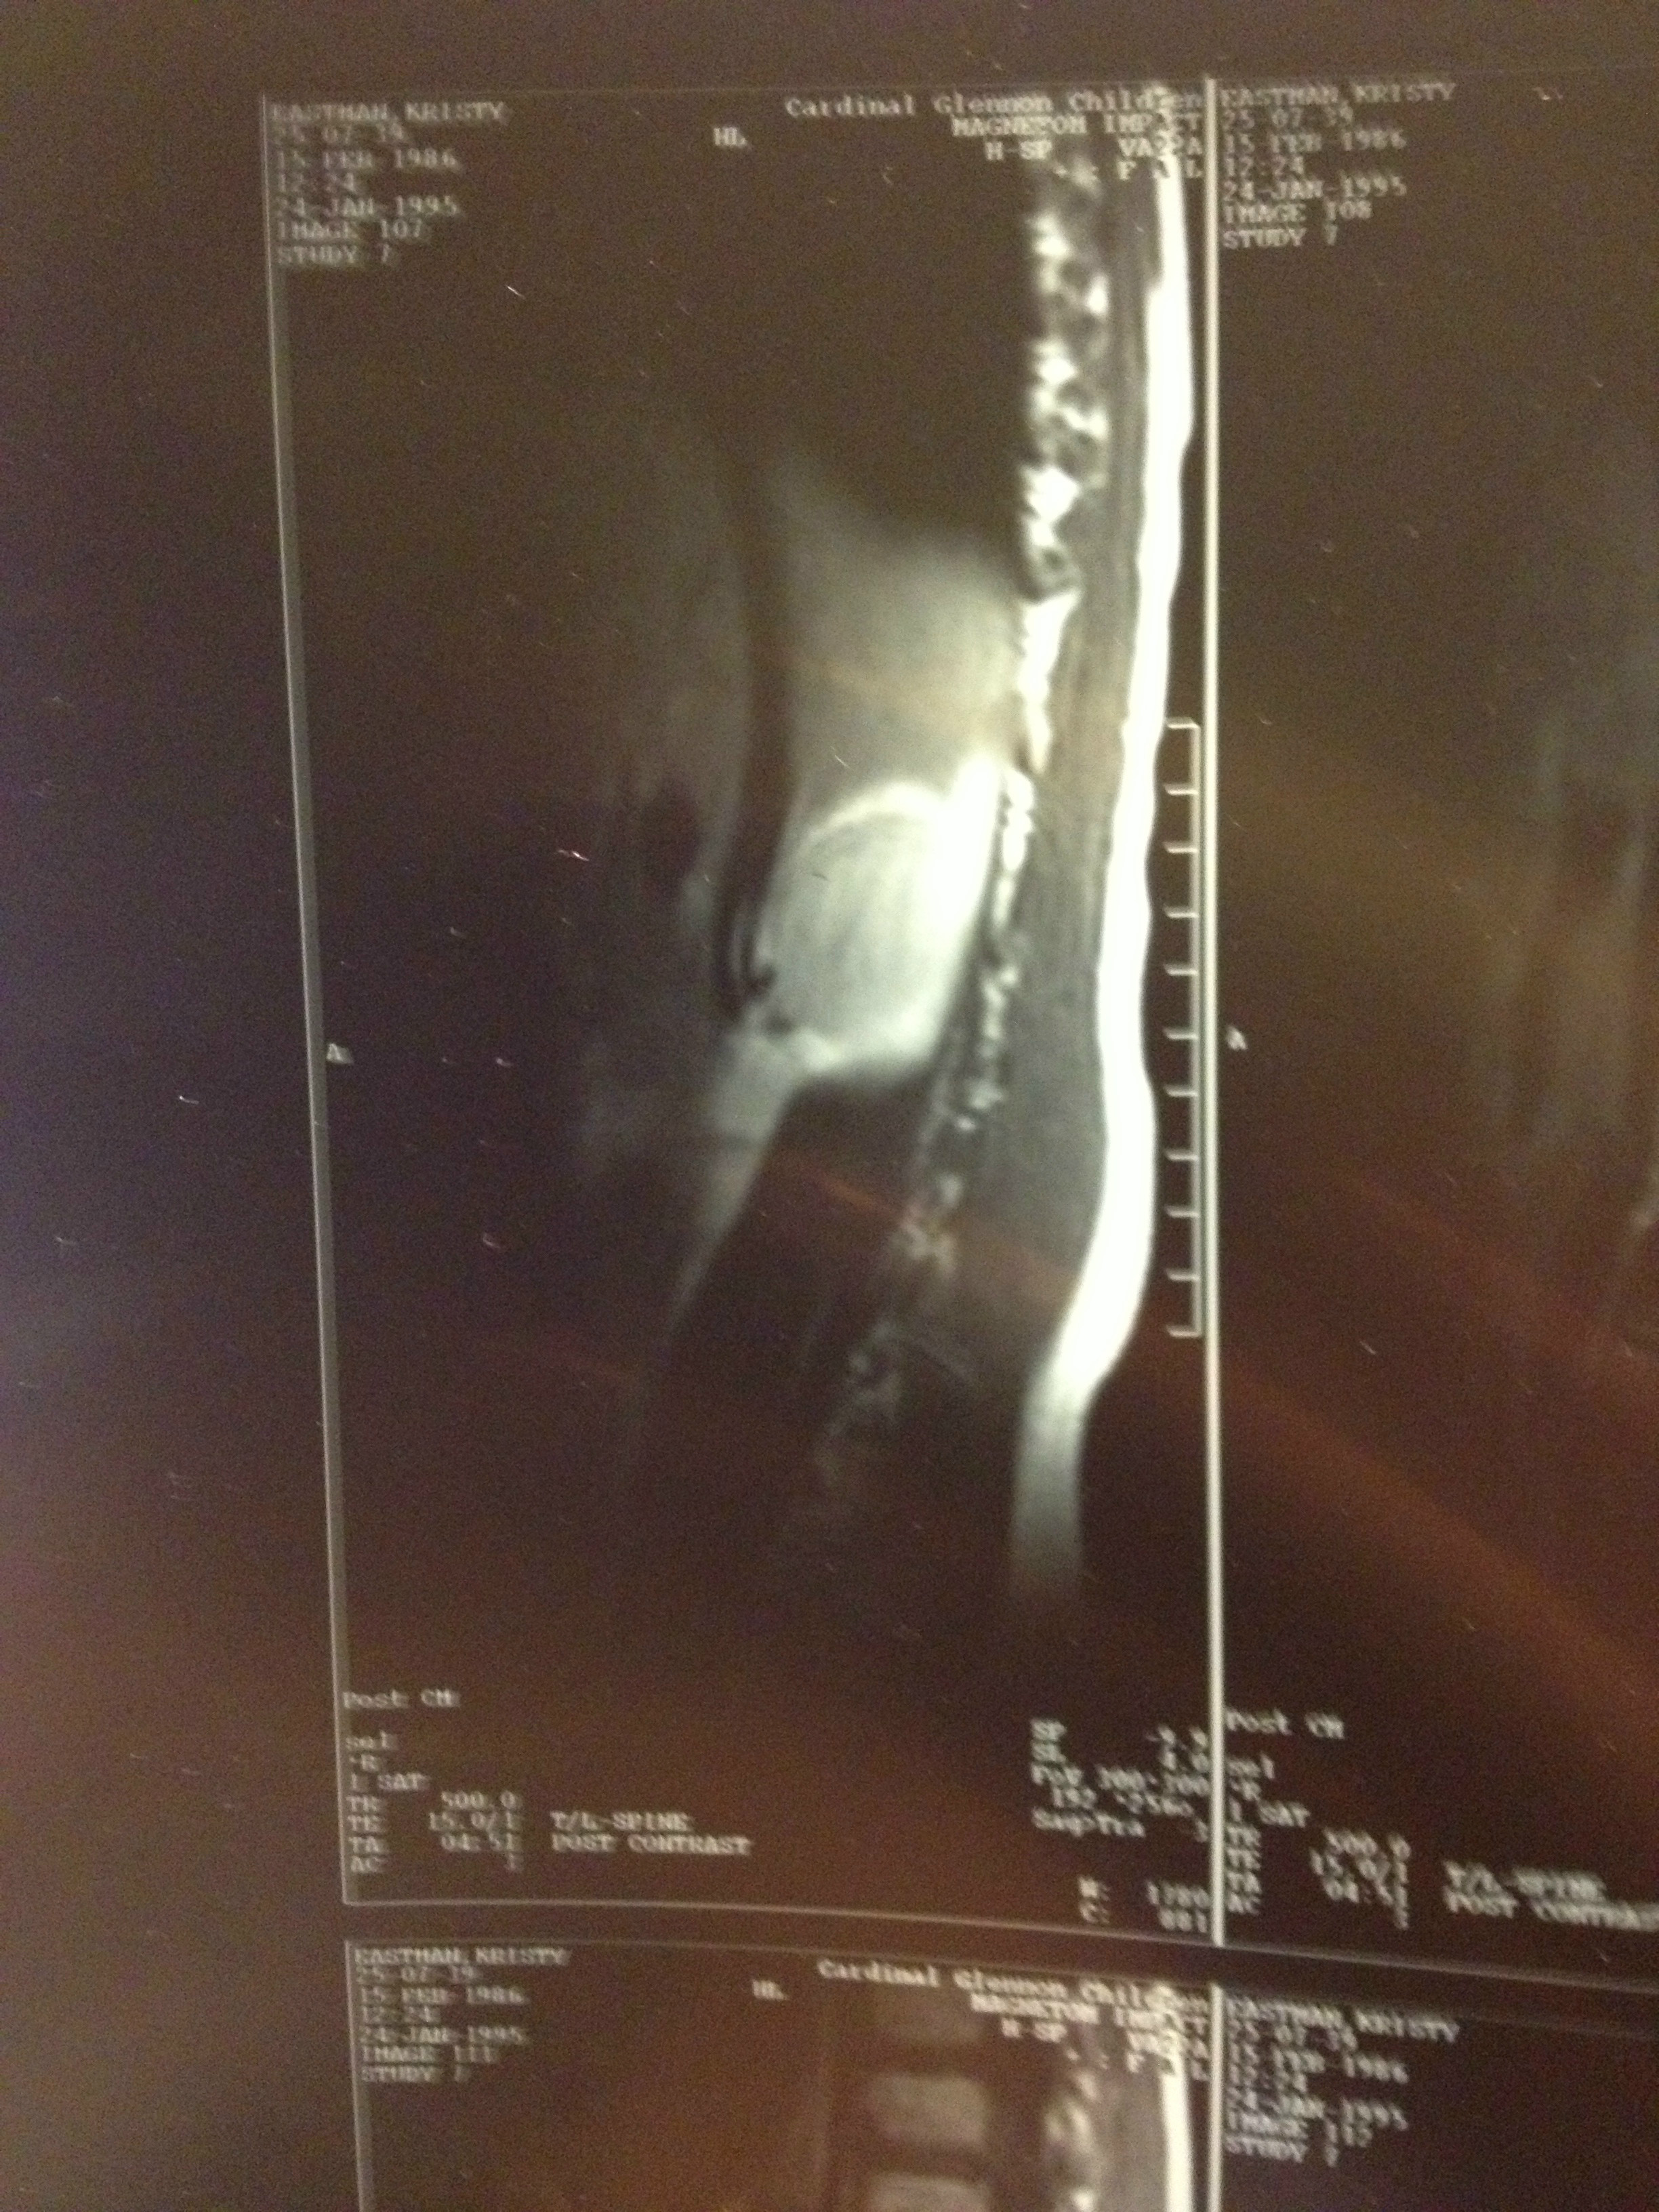

I'm Kristy. I was born with a benign spinal cord astrosytoma, a rare tumor that grew inside of my spinal cord. The doctor told my parents when they discovered the tumor that I had a better chance of winning the New York lottery than having the type of tumor in the location that I had it. I've had three tumor removal surgeries due to the tumor growing back several times and a lifetime supply of radiation treatment to kill it and prevent from growing any further. I've had 19 surgeries total, including rods inside my back, a spinal fusion for scoliosis, two leg lengthenings, and a foot reconstruction. Due to all of the surgeries and complications from the tumor, I was told I would never walk again. I've beaten the odds several times, and have learned to walk all over again starting from a wheelchair, to a walker, then to a cane and now just a full length KAFO leg brace. I am physically disabled on the left side of my body and walk with a limp.